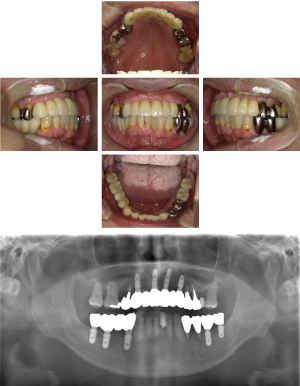

60代 女性 全顎 インプラント サイナスリフト等

| 年代・性別 | 60代・女性 |

|---|---|

| 主訴 | 上顎の入れ歯が割れた。リンゴやおかきを食べられるようになりたい。 |

| 部位 | 右上④3②・左上②3④5⑥のブリッジ |

| 治療期間 | 2年 |

| 費用 | ¥2,447,500(税込) |

| 副作用・リスク |

|